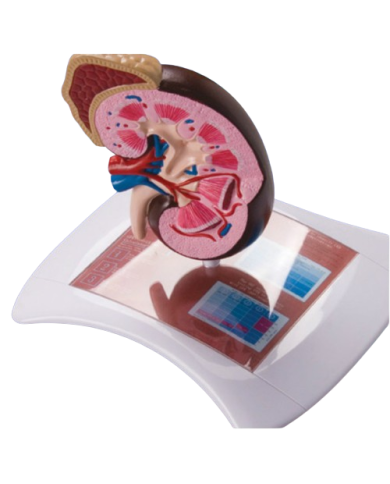

Modello anatomico PER FORNITURE CASE FARMACEUTICHE

Modello anatomico PER FORNITURE CASE FARMACEUTICHE

Modello anatomico PER FORNITURE CASE FARMACEUTICHE

Modello anatomico PER FORNITURE CASE FARMACEUTICHE

Modello anatomico PER FORNITURE CASE FARMACEUTICHE

Modello anatomico PER FORNITURE CASE FARMACEUTICHE

Modello anatomico PER FORNITURE CASE FARMACEUTICHE

Modello anatomico PER FORNITURE CASE FARMACEUTICHE

Modello anatomico PER FORNITURE CASE FARMACEUTICHE

Modello anatomico PER FORNITURE CASE FARMACEUTICHE

Modello anatomico PER FORNITURE CASE FARMACEUTICHE

Modello anatomico PER FORNITURE CASE FARMACEUTICHE

Modello anatomico PER FORNITURE CASE FARMACEUTICHE

Modello anatomico PER FORNITURE CASE FARMACEUTICHE

Modello anatomico PER FORNITURE CASE FARMACEUTICHE

Modello anatomico PER FORNITURE CASE FARMACEUTICHE

Modello anatomico PER FORNITURE CASE FARMACEUTICHE

Modello anatomico PER FORNITURE CASE FARMACEUTICHE

Modello anatomico PER FORNITURE CASE FARMACEUTICHE

Modello anatomico PER FORNITURE CASE FARMACEUTICHE

Modello anatomico PER FORNITURE CASE FARMACEUTICHE

Modello anatomico PER FORNITURE CASE FARMACEUTICHE